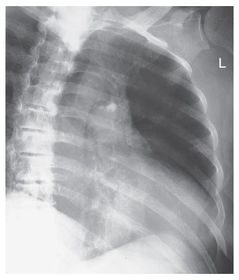

A patient enters the ER with a Fx rib and possible hemothorax/pneumothorax; which projection/position will be ordered along with the routine rib study? PA and Lateral CXR